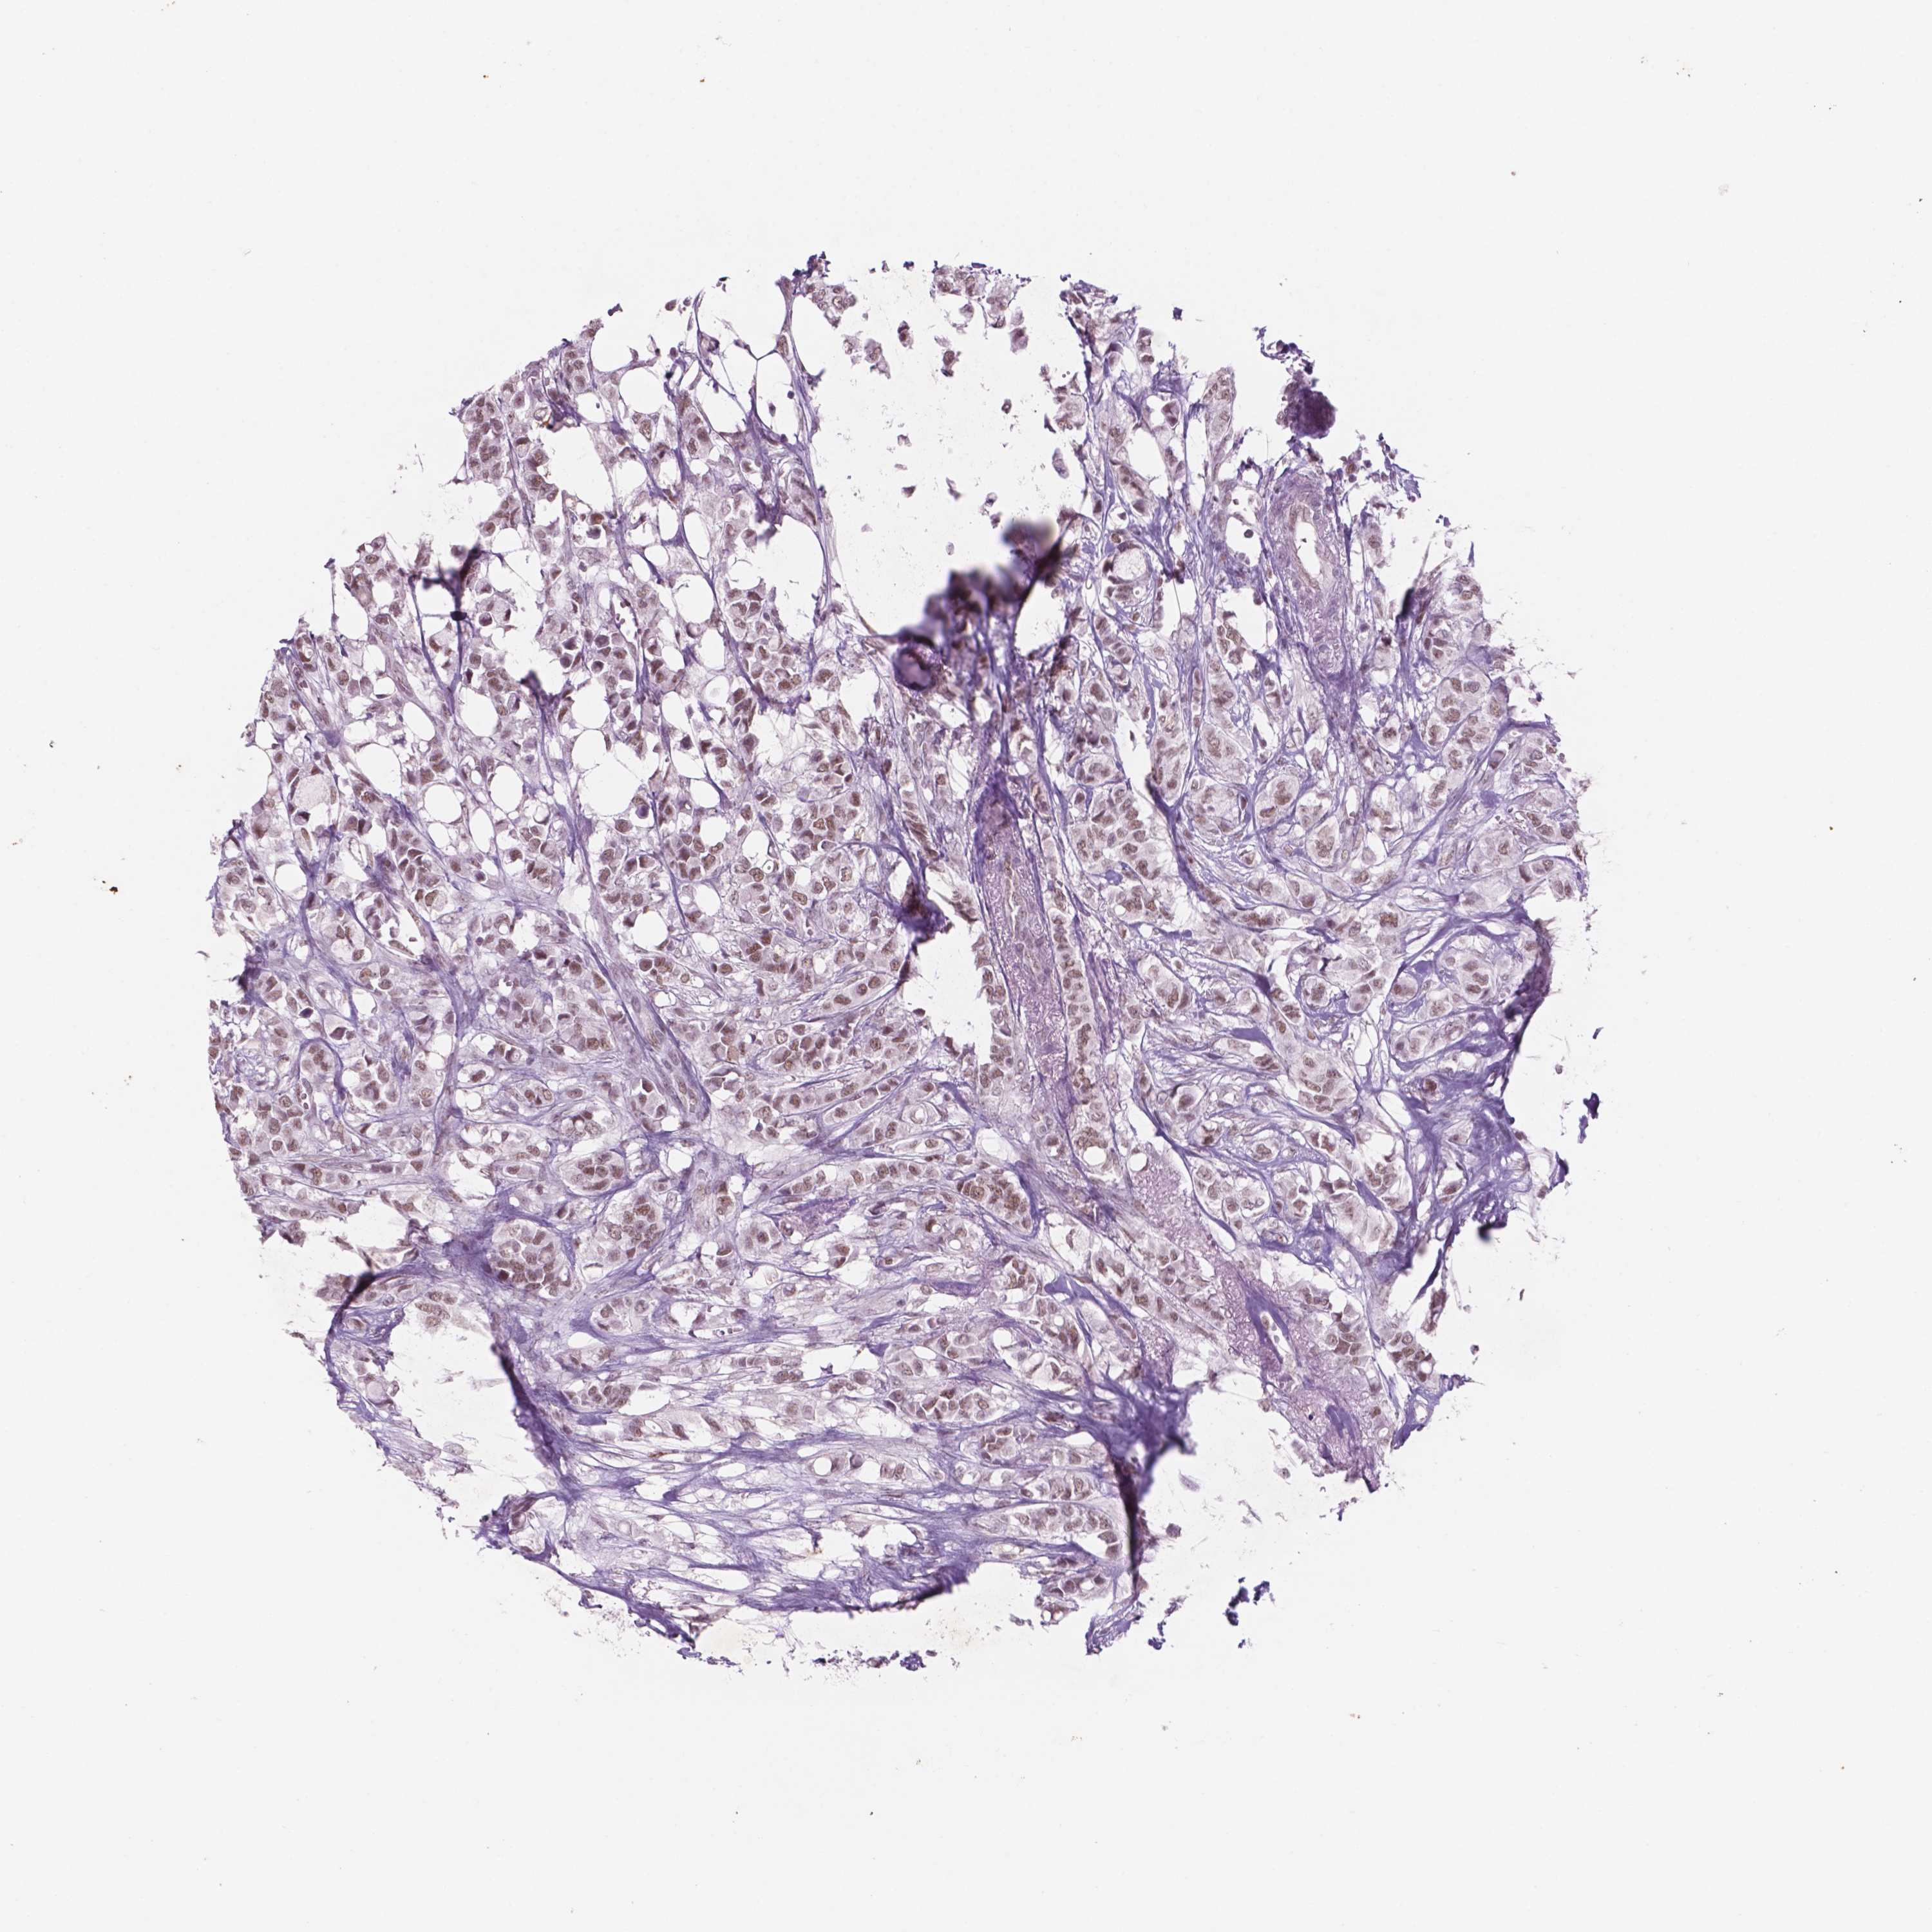

BRCA TCGA BRCA VALIDATION PROTEIN EXPRESSION

ANTIBODIES

AND

VALIDATION